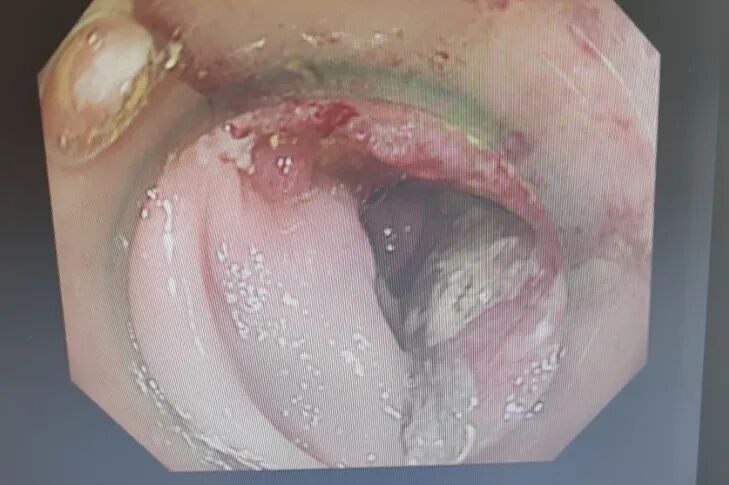

内容提要 近日,葫芦岛市第二人民医院胃肠外科乔世峰教授团队凭借过硬的微创诊疗技术与一站式全程服务,成功为一名八旬高龄晚期直肠恶性肿瘤患者实施根治手术,用专业实力打破异地就医困局,收获了患者及家属百分百的信任与认可。 Part.01 一条出诊信息,明确就诊方向 李大爷年近八旬,便血症状持续5个月,起初并未引起足够重视。直到肠镜检查结果出来,家人才意识到病情的严重性:肿瘤已环绕肠腔三分之二,病理为腺癌,治疗刻不容缓。 🔺入院时患者肠镜(左)及影像照片(右) 考虑到老人年事已高,家属多方打听,希望能找到此领域的权威专家为老人手术。几经辗转,他们认定了辽西地区胃肠外科权威专家——锦州附属医院胃肠外科乔世峰主任。正当家属做好带着老人奔赴外地手术的准备时,一条消息让他们欣喜若狂:乔世峰主任已全职加盟葫芦岛市第二人民医院,于是当即带着检查报告前来就诊。 Part.02 微创精准施治 小切口解决大问题 结合患者肿瘤情况及高龄身体基础,乔世峰主任、张凯副主任带领团队为患者量身制定了腹腔镜微创根治手术方案。相较于传统开腹手术,腹腔镜微创手术具有创伤小、出血少、恢复快的显著优势。对于高龄中晚期肿瘤患者而言,该术式既能实现肿瘤的彻底切除与区域淋巴结清扫,又能最大程度保护肠道正常功能,减少术后并发症,为后续康复与辅助治疗奠定坚实基础。 术中,团队借助腹腔镜高清视野,顺利完成肿瘤切除、淋巴结清扫及肠道吻合,最大限度保留了正常组织。整台手术出血量仅10毫升,真正实现了“小切口解决大问题”。 Part.03 一站式诊疗暖人心 优质服务获盛赞 手术成功是治疗的第一步,规范的术后辅助治疗关乎患者长期预后。术后,科室迅速联合肿瘤内科开展多学科会诊,依据病理及免疫组化结果,为患者量身制定化疗方案,实现“手术+化疗+康复”一站式全程诊疗服务,让患者少奔波、更安心,有效降低复发风险,提升治愈希望。 “原本已经做好去外地手术的准备,没想到乔主任就在家门口。手术做得好,后续治疗也安排得明明白白,我们全家都特别放心。”李大爷的家属由衷感谢道。 Part.04 深耕胃肠肿瘤近40年 顶级专家坐阵“家门口” 乔世峰教授深耕胃肠肿瘤规范化治疗与疑难病例诊治近40年,是省内较早开展腹腔镜胃肠肿瘤微创手术的权威专家,在辽西地区享有盛誉。此次全职加盟,将有力推动市二院胃肠外科诊疗水平提质升级,更好满足群众的就医需求。如今,患者无需远赴外地奔波求医,在家门口就能享受到高水平、精准化的优质诊疗服务。葫芦岛市第二人民医院胃肠外科以实际行动践行“大病不出市”的承诺,让更多患者在家门口就能看得好病、安心康复。 Part.05 人民医院 人民名医 乔世峰 博士后 主任医师 教授 硕士研究生导师 ·葫芦岛市第二人民医院胃肠外科主任 ·原锦州医科大学附属第一医院胃肠外科主任 ·首都医科大学医学博士、天津医科大学博士后 ·辽宁省医学会外科分会疝与腹壁外科学组委员 ·辽宁省医学会肠外肠内营养学会委员 ·东北三省肠外肠内营养支持专业委员会委员 ·辽宁省中西医结合学会肿瘤专业委员会常委 ·《中国肿瘤生物治疗杂志》特约审稿专家 专业特色:省内胃肠外科领域领军专家,从事普外科工作近40年,擅长胃肠道多发、疑难病诊治,精通普外科各类手术,如胃癌、结肠癌、疝、肠梗阻、肝癌、胆囊切除术、胰腺手术等。深耕胃肠道肿瘤规范化治疗与微创技术创新,在省内较早开展腹腔镜微创胃肠肿瘤手术,具有极高造诣。在国家核心期刊发表学术论文20余篇,SCI论文10余篇。 张凯 副主任医师 硕士研究生 ·葫芦岛市第二人民医院胃肠外科副主任 ·辽宁省生命科学学会胃肠肿瘤专业委员会委员 ·中医临床药学分会委员理事 ·沈阳市抗癌协胃癌专业委员会委员 专业特色:以腹部外科为诊治方向,擅长普通外科多发及疑难病的诊断、治疗和手术。以微创技术为特色优势,擅长腹腔镜阑尾切除术、腹股沟疝修补术、结直肠癌根治术、胃癌根治术。先后发表论文2篇,完成“腹腔镜、胆道镜及两镜联合手术临床应用”科研项目,并获得了葫芦岛市科学技术成果奖励二等奖,学术论文类获得葫芦岛市自然科学学术成果一等奖。